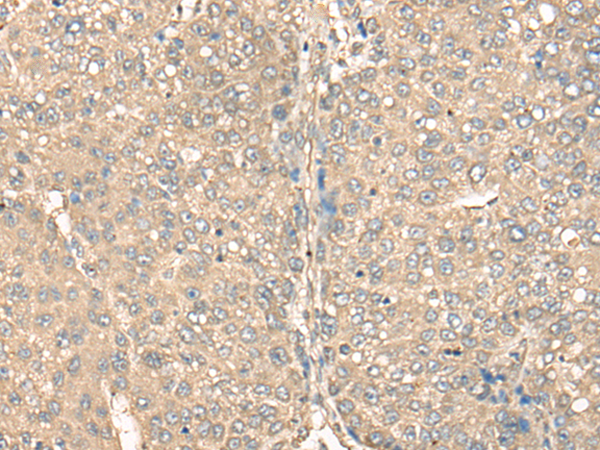

ELISA, IHC |

IHC positive control: |

Human liver cancer and human brain |

IHC Recommend dilution: |

25-100 |